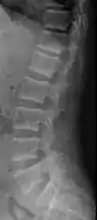

X-ray of a subtle "rugger jersey spine" due to sclerotic bands adjacent to the vertebral endplates.[17]

CT scan of the same case.[17]